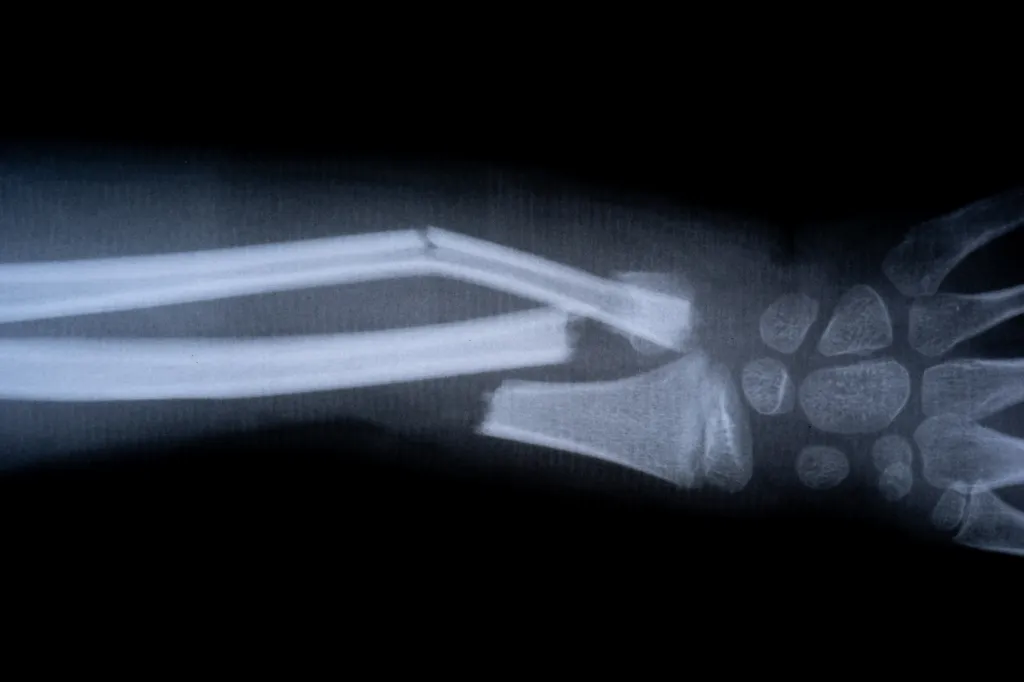

Scientists in China have unveiled a groundbreaking “bone glue” that can heal fractures within minutes, cutting down recovery times that would normally take months.

The product, called Bone-02, was developed by a research team aiming to reduce the need for invasive orthopedic surgeries that often involve metal plates and screws, according to New York Post.

According to Lin Xianfeng, associate chief orthopedic surgeon at Sir Run Run Shaw Hospital in Hangzhou, the adhesive works in blood-rich environments and can fix shattered bone fragments in just three minutes with a single injection.

In one trial, a patient with a wrist fracture was treated through a small incision and healed in minutes — avoiding the need for plates, screws, and follow-up surgeries. Three months later, doctors confirmed the bone had healed fully without complications.

Researchers drew inspiration from oysters, which naturally produce a glue-like substance strong enough to stick to underwater surfaces. Similarly, Bone-02 forms erosion-resistant bonds and has been shown to withstand forces of over 400 pounds.

The glue is also naturally absorbed by the body during healing, meaning patients won’t need an additional procedure to remove implants. Early results suggest it carries fewer risks of infection compared to traditional metal-based treatments.